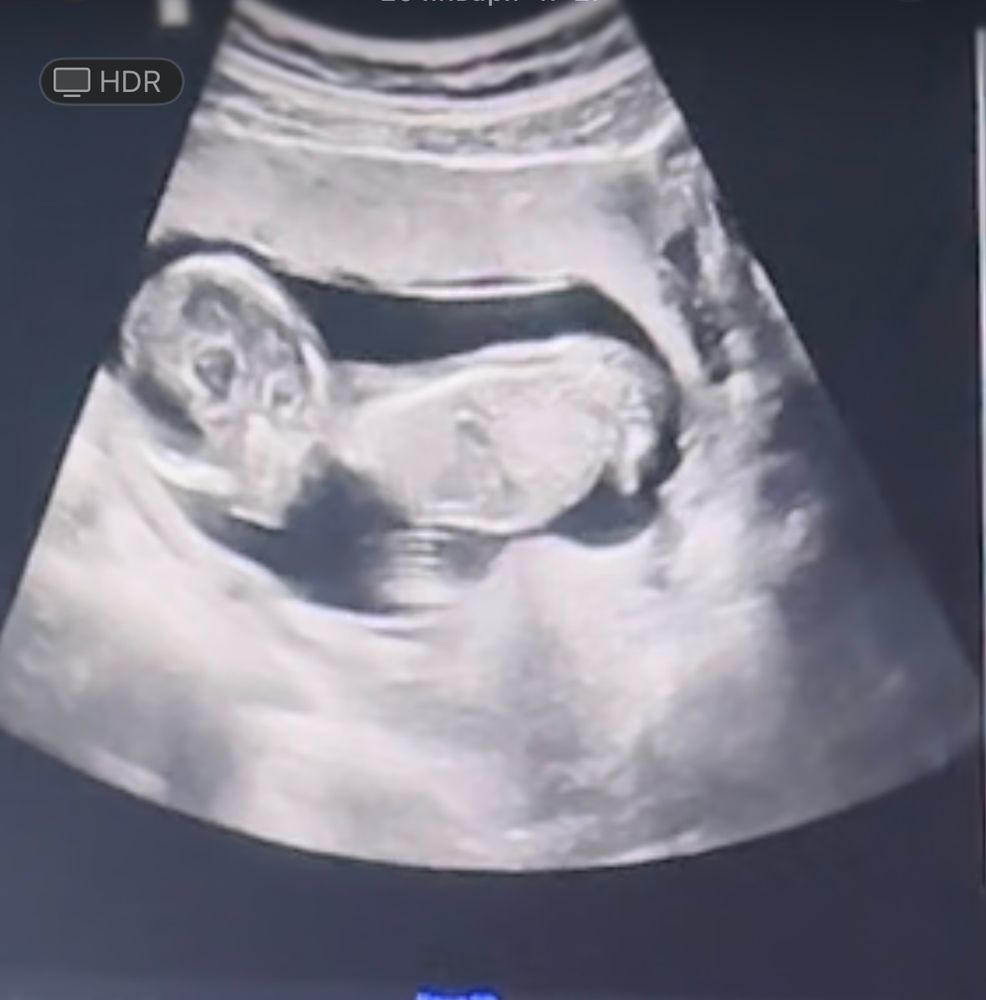

Определите пол по узи)) 1 скрининг 🩷

Это половой бугорок? Кто разбирается?

Ой да не поймешь так, могли ноги так на узи отражаться. Так в сказали вам пол в итоге? Если бугорок, то я сказала бы мальчик.

Если это половой бугорок, то 100% мальчик